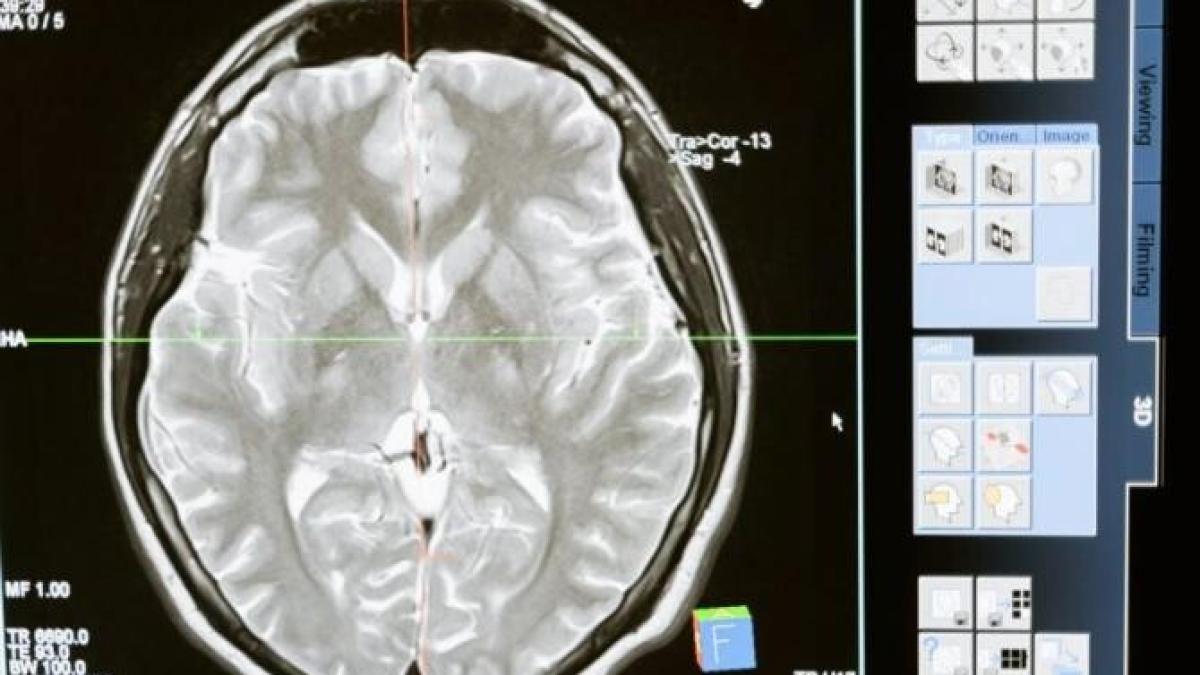

Mereu îți promiți că vei merge la sală și vei face sport? Deseori te lași păgubaș? Oamenii de știință au descoperit circuitul din creier care se ocupă cu executarea mișcărilor pe care ți le-ai propus.

Mișcarea planificată de tip fitness, aerobic sau alte discipline este esențială pentru viața noastră de zi cu zi și are adesea o execuție întârziată. În copilărie așteptam strigătul de ”START!” înainte de a alerga într-o întrecere. Ca adulți, așteptăm până când semaforul devine verde înainte de a face un viraj. În ambele situații, creierul a planificat mișcările noastre precise, dar le suprimă execuția până la un indiciu specific (de exemplu, strigătul ”START!” sau lumina verde). Acum, oamenii de știință au descoperit rețeaua creierului care transformă planurile în acțiune ca răspuns la acest indiciu.

De exemplu, cortexul motor este o zonă a creierului care controlează mișcarea. Tiparele de activitate în cortexul motor sunt dramatic diferite între fazele de planificare și execuție ale mișcării. Tranziția între aceste modele este esențială pentru a declanșa mișcarea. Cu toate acestea, zonele creierului care controlează această tranziție erau necunoscute.

Oamenii de știință au corelat apoi modele complexe de activitate neuronală cu etapele relevante ale sarcinii comportamentale. Cercetătorii au descoperit că activitatea creierului are loc imediat după inițiativa și în timpul comutării între planificarea motrică și execuție. Această activitate a creierului a apărut dintr-un circuit de neuroni din mijlocul creierului, talamus și cortex.

”Am găsit un circuit care poate schimba activitatea cortexului motor de la planificarea motorie la execuție la momentul potrivit. Acest lucru ne oferă o perspectivă asupra modului în care creierul orchestrează activitatea neuronală pentru a produce un comportament complex. Lucrările viitoare se vor concentra pe înțelegerea modului în care acest circuit funcționează și reorganizează activitatea neuronală în multe regiuni ale creierului”, a mai spus dr. Inagaki.